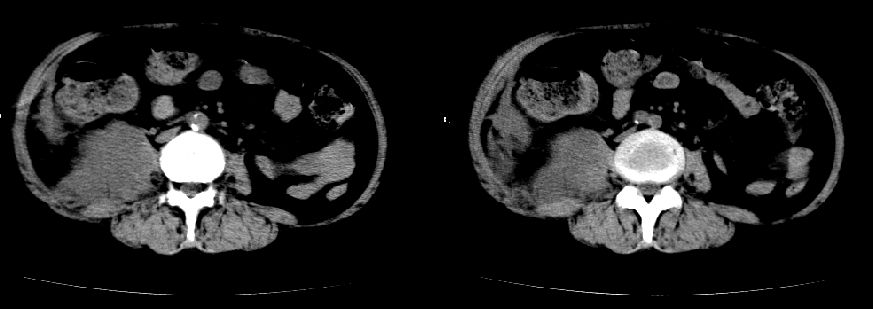

以下是引用liuyue在2008-7-19 10:17:00的发言:[br]考虑:1.肾周脓肿,肾实质、腰大肌及侧腹壁均受累及。 2.右肾囊肿。[br]建议:强化扫描,除外肾癌之可能。[br]

以下是引用zhengfaming在2008-7-19 14:48:00的发言:[br]右肾脓肿并感染可能性大,建议增强

以下是引用江广1996在2008-7-19 10:48:00的发言:[br]先考虑右侧肾周感染脓肿形成并累及腰大肌,右肾前侧有病灶考虑囊肿。